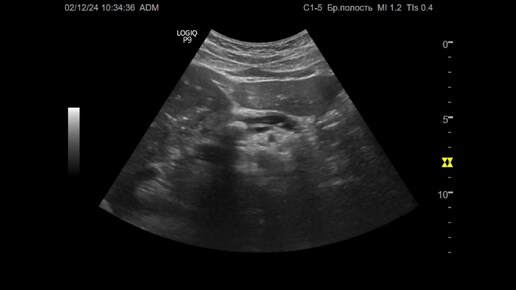

Ультразвуковая диагностика (УЗИ). Доктор Иогансен. Видеопримеры. Выпуск 108. Панкреатолитиаз (2).